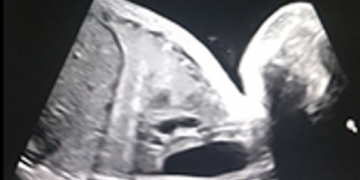

Guida al Counselling di Maggio 2025: patologie cistiche della fossa cranica posteriore

Cari colleghi, vi presentiamo la guida al counseling di Maggio 2025 sulla Patologia cistica della fossa cranica posteriore. Potrete scaricarla cliccando sul link. Grazie a Laura Sarno! ...